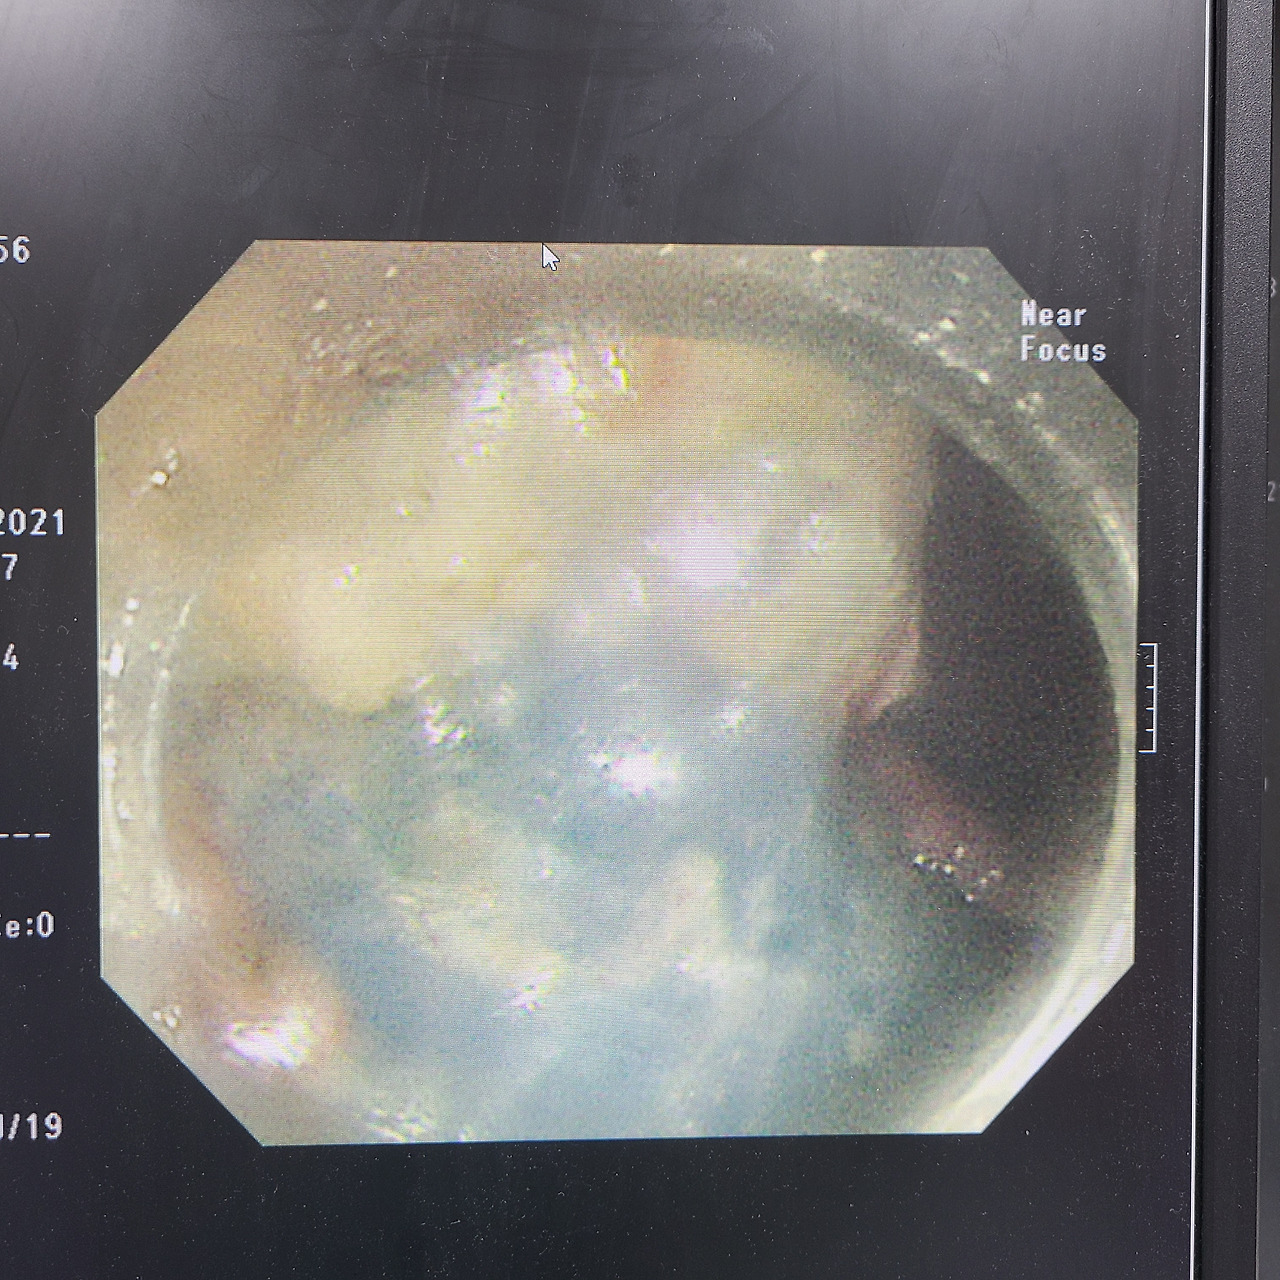

문제는 두 번째 환자였다. 위치가 어렵고 병변도 크기 때문에 시간이 올래 걸릴 거란 예상을 했지만 의외의 복병이 있었다. fat 때문에 시술 시간이 길어지고 있었다. 내시경 화면을 아무리 씻어도 화면이 흐렸으며 dissection을 할 때마다 fat이 튀어서 내시경 렌즈를 씻어도 씻기지가 않았다. 심안으로 내시경을 봐야 한다며 진담 섞인 농담을 건네가며 시술을 했다. 눈에 보일 정도로 fat이 그득했고 병변을 절제하는 순간마다 화면을 흐리게 만들었다. 원래 내시경 화면이 저렇게 뿌옇지 않고 선명한데 지방으로 인해 화면이 뿌옇게 보이는 것이다. bleeding cotrol은 다른 내시경실 임상교수님이 하셨는데 fat이 이렇게나 많다는 것을 이야기해 드리고 나중에 coagrasper forcep으로 fat 부분을 소작할 때 기름이 튀는 모습을 볼 수 있을 거라며 이야기해 드렸다. 아니나 다를까 화면을 가리며 기름이 튀는 게 느껴졌으며 기름이 지글지글 잘 올라온다며 농담을 하며 2시간이 지나서야 시술은 끝났다.